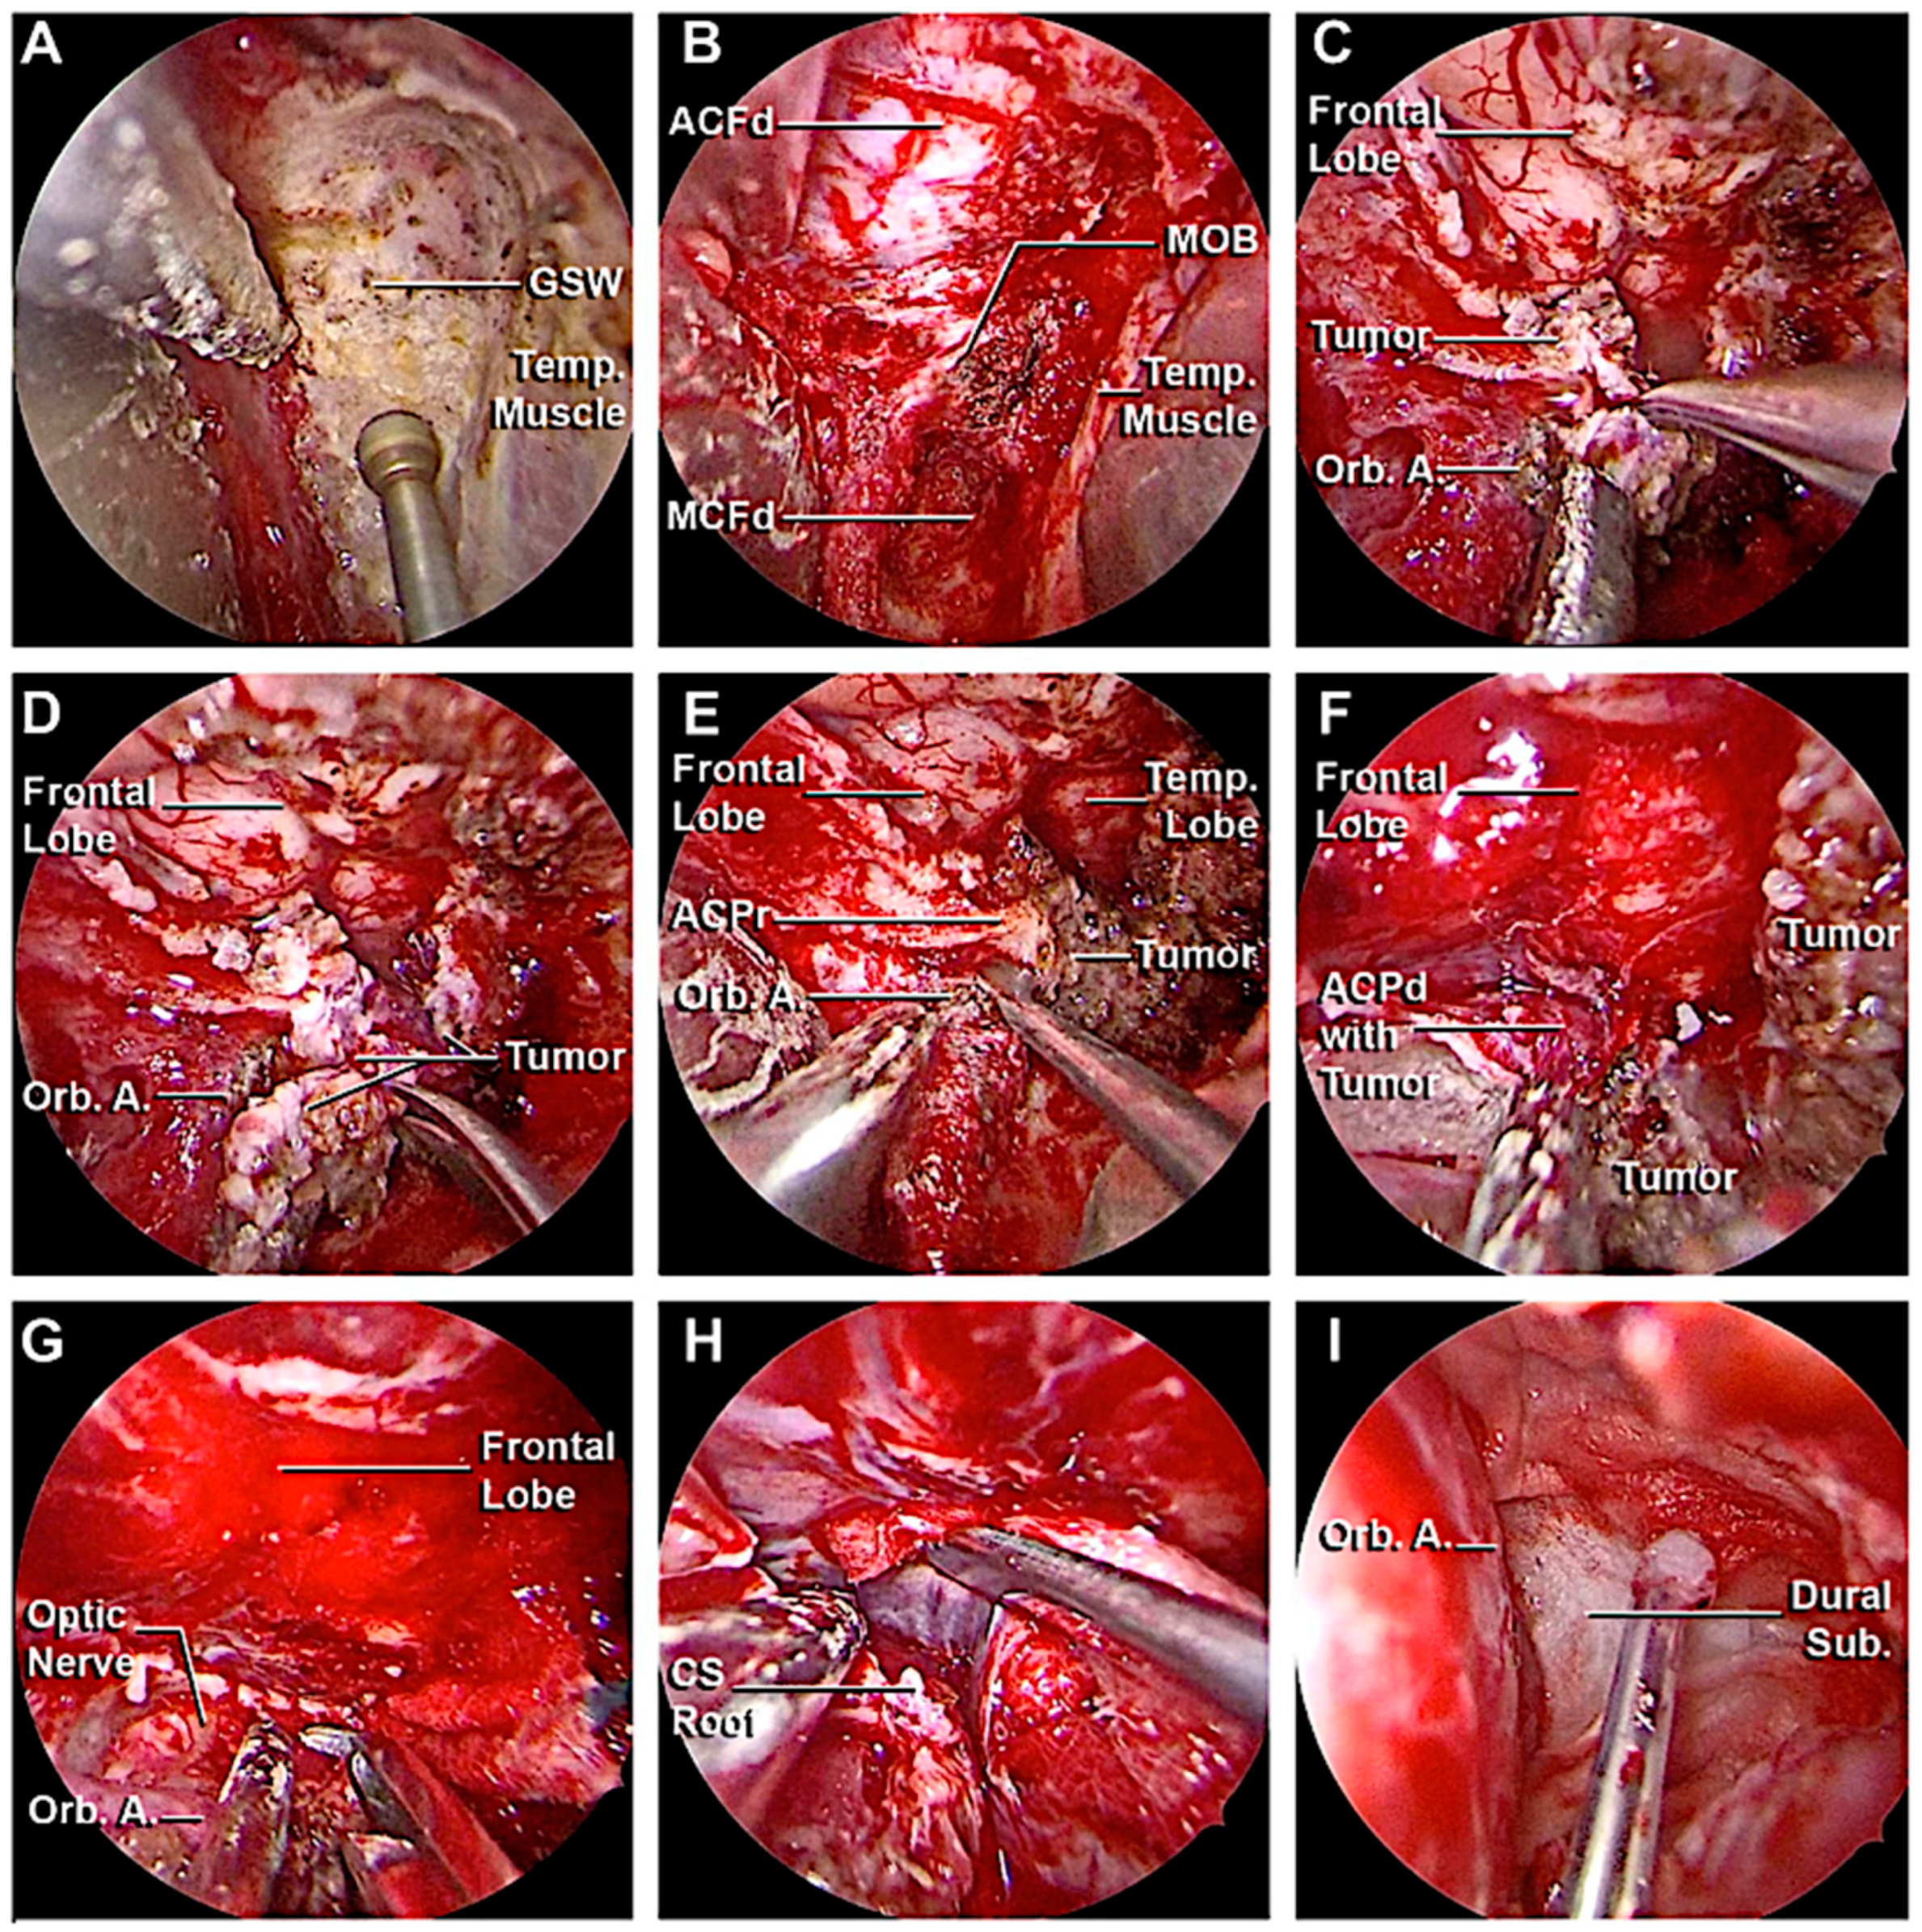

3.3. Clinical Cases

3.3.1. Case 1

3.3.2. Case 2

3.3.3. Case 3